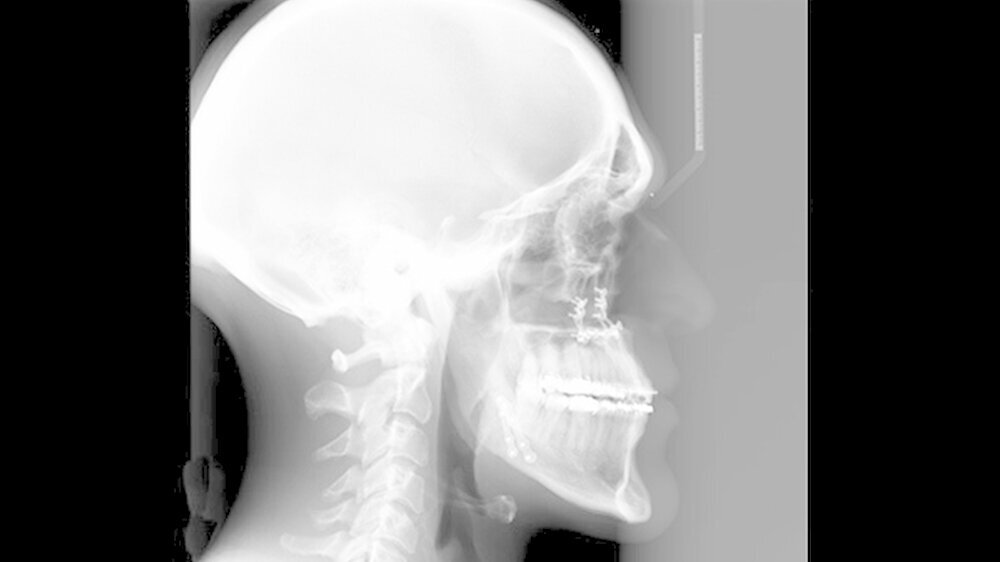

Das deutlich harmonischeres Profil drei Monate nach der Operation: Im Mai des nachfolgenden Jahres wurden die Metallplatten in einem ambulanten Eingriff wieder entfernt. Eine Multibandapparatur hält die Zähne noch "in der Reihe". Der Patient kann heute dank der individuellen innovativen Behandlung ein normales Leben führen, die Gesichtsästhetik und seine Kaufunktion sind vollständig wiederhergestellt.

Nach dreidimensionaler Planung im zahntechnischen Labor, in dem die Bissschlüssel konventionell hergestellt wurden, wurden dann ein Jahr später beide Kiefer operativ mobilisiert. Hierzu wurde von einem Schnitt im Mund der Oberkieferknochen freigelegt.

Mit einer Säge wurde ein gezielter Knochenschnitt durchgeführt. Nach der Präparation wurde der zahntragende Abschnitt des Oberkiefers vom restlichen Gesichtsschädel gelöst. Erst wurde die Bisssituation anhand des Bissschlüssels exakt eingestellt, dann mit 2 mm dicken Osteosyntheseplatten aus Titan der Knochen in der neuen Position mithilfe von Titanschrauben fixiert.

Im Unterkiefer erfolgte dann die Schnittführung im Zahnfleisch hinter dem letzten Backenzahn beidseits. Nun wurde der Unterkiefer mit spezieller Technik durchtrennt um die zahntragende Basis vom gelenktragenden Knochenabschnitt des Unterkiefers zu verschieben. Bei der Präparationwurde der im Unterkieferknochen verlaufende Gefühlsnerv der Unterlippe sorgfältig geschont.

Die neue Position wurde mit einem zweiten Bissschlüssel, der die endgültige Bisssituation einstellt,zugeordnet und mit Osteosyntheseplatten und -schrauben gesichert. Die Operation ging mit einem stationären Aufenthalt von nur fünf Tagen einher.